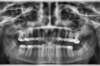

Encombrements traités par gouttières

E-Intermédiaire 1